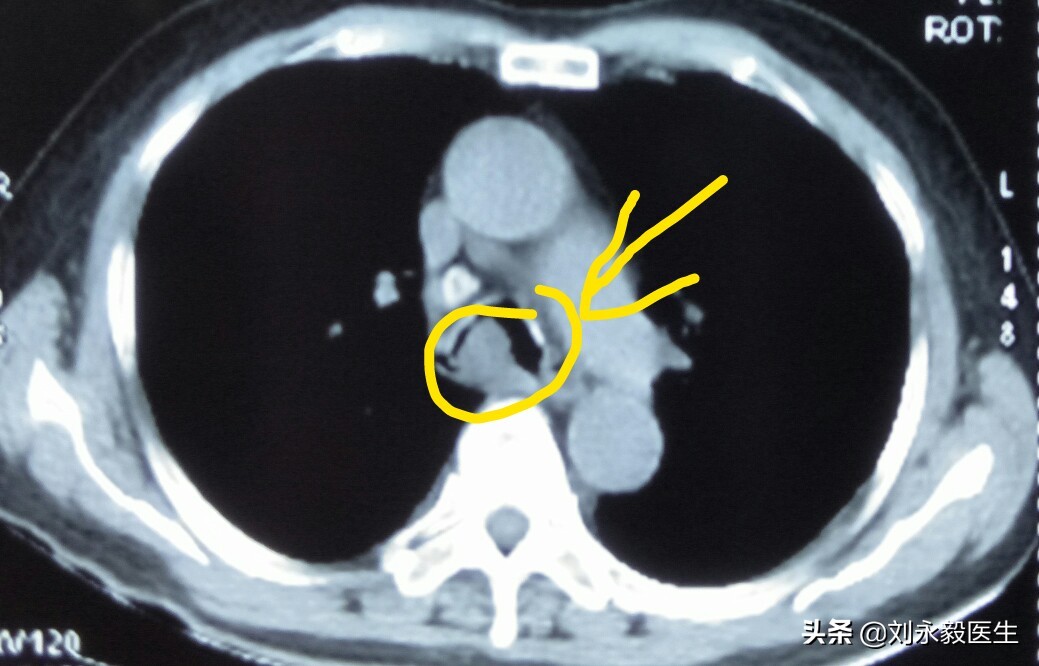

上圖是某患者初診肺癌時的胸部CT,腫瘤不大,如果此時手術,生存時間可能要好很多,很遺憾,采取了“中藥化療”,2018年11月胸悶氣短,檢查CT發現氣管隆突處腫瘤堵塞主支氣管,如下CT圖。

這時如果給予介入支架等辦法,病人有可能還會持續一些時日的,很遺憾病人在憋悶、痛苦中度過了最后半個月。